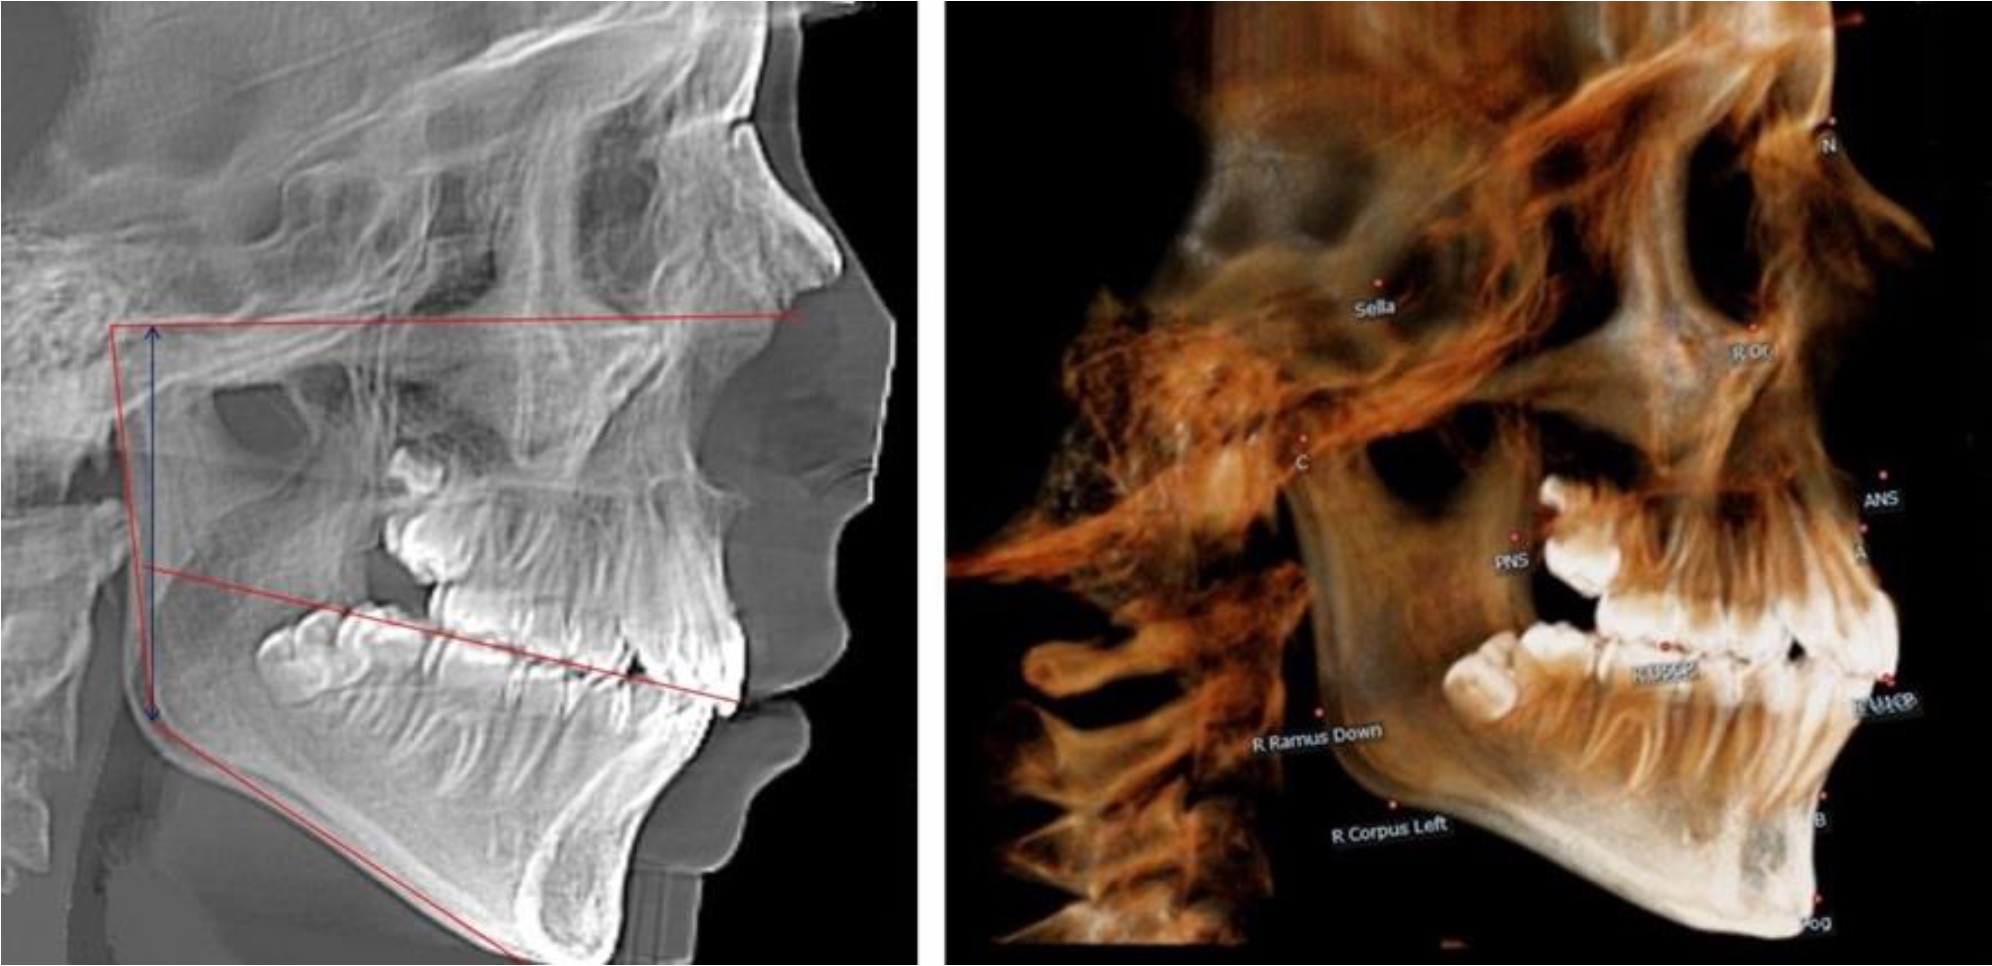

На боковых телерентгенгенограммах вершину суставной головки обозначали точкой кондиион Cond. Касательные линии к ветви и телу нижней челюсти пересекались в точке, которую обозначили Go. Точкой hPOcP обозначали дистальный бугорок нижнего второго моляра вблизи окклюзионного контура коронки. Указанный ориентир соединяли с межрезцовой точкой при построении окклюзионной линии. Высота ветви определялась расстоянием Go-Cond. Окклюзионная линия служила границей между верхней (окклюзионно-суставной) линией и нижней (окклюзионно-альвеолярной) линией.

В 1-й группе были проанализированы 7 телерентгенограмм и 7 ортопантомограмм, что составило (6,60 ± 2,41) % от числа изученных рентгенограмм. На всех парах рентгенограмм угол нижней челюсти, измеренный на телерентгенограмме, соответствовал углу, полученному при построении угла на ортопантомограмме. Окклюзионная линия практически однотипно делила ветвь на два отдела (рис. 1).

Как на ортопантомограмме, так и на телерентгенограмме высота ветви у детей в периоде сформированного прикуса молочных зубов составляла (42,21 ± 2,48) мм. При этом высота верхней окклюзионно-суставной части была (22,57 ± 1,46) мм, а нижней – (19,64 ± 1,54) мм.

Учитывая вариабельность абсолютных величин, определи относительные показатели соразмерности частей ветви нижней челюсти. Так, отношение высоты верхней части ветви к нижней в среднем составляло 1,15 ± 0,13. Отношение общей высоты ветви к верхней ее части составляло 1,87 ± 0,14, а отношение общей высоты ветви к нижней ее части было 2,14 ± 0,16 и достоверных различий по относительному показателю отношения всей высоты к верхней и нижней челюсти нами не отмечено (р ˃ 0,05). При этом визуально обе части выглядели примерно равноразмерными.

Рис. 1. ТРГ и ОПТГ пациента 1-й группы